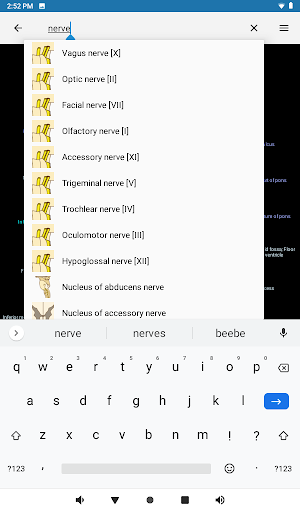

- Localice fácilmente las estructuras anatómicas gracias a la búsqueda de índice

*Encuentre sus partes anatómicas más fácilmente gracias a la nueva función de búsqueda, más intuitiva y poderosa.